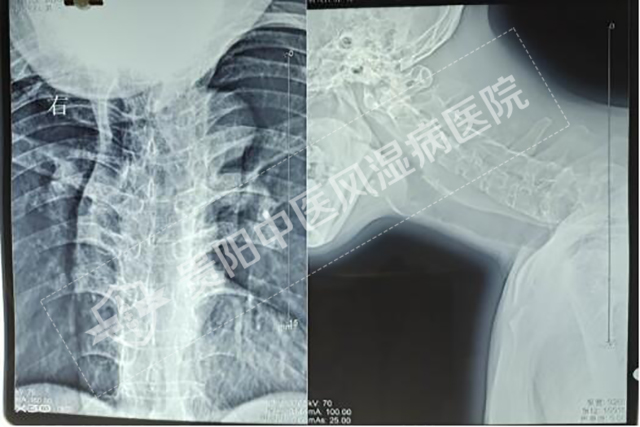

強直性脊柱炎——青年男性致殘殺手

強直性脊柱炎是一種以脊柱為主要病變的慢性疾病,是遺傳和環(huán)境等多種因素共同作用引發(fā)的,主要累及脊柱、骶髂關(guān)節(jié),引起脊柱強直,活動困難,并可有不同程度的眼、肺、心血管、腎等多個器官損害。

強直性脊柱炎患者影像1.jpg

強直性脊柱炎患者影像2.jpg

強直性脊柱炎患者影像